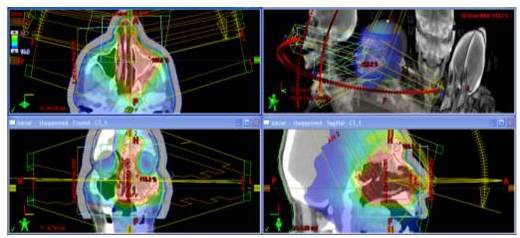

GASTROINTESTINAL

Al igual que le caso de lesiones en SNC, la RAVM se emplea para disminuir la dosis en estructuras cercanas a la lesión con tolerancias menores a la dosis de tratamiento (asas delgadas, hígado, riñones, etc.). El paciente se dispone en posición supina y se emplean arcos axiales con energía de Rayos X de 6 MV. Al igual que en los casos anteriores existe una reducción de alrededor de 14 min (10).

A continuación se muestra el plan de tratamiento en plano axial, coronal y sagital para una lesión de estómago.

GINECOLÓGICAS

RAVM ofrece al igual que en otras áreas la posibilidad de obtener altas dosis en el volumen blanco y minimizar al mismo tiempo la dosis a estructuras riesgo. Se usan Rayos X de 6 MV y el paciente se posiciona decúbito supino. Se emplean 2 arcos axiales (camilla en 0°) parciales con ángulos de inicio y finalización de 150° y 210° para de esta manera minimizar la dosis en el recto. Al igual que en los casos anteriores existe una reducción de alrededor de 14 min.

En la siguiente Figura se observa el plan de tratamiento en plano axial, coronal y sagital para el tratamiento de una lesión en cuello uterino.